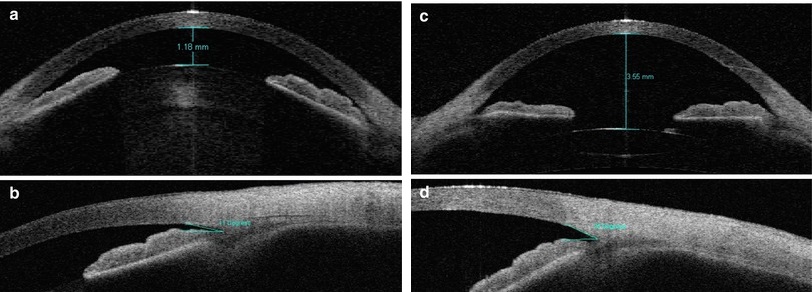

6. 백내장 수정체 적출술

백내장 수술 즉 수정체 적출술 및 인공수정체 삽입술 만으로도,

폐쇄각녹내장치료에 도움이됩니다.

폐쇄각 녹내장의 원인 자체가 수정체의 팽대로 인한 수정체-홍채의 접촉이기에,

팽대된 백내장을 제거하고 , 얇은 인공수정체로 교환하면, 폐쇄각 녹내장이 치료됩니다.